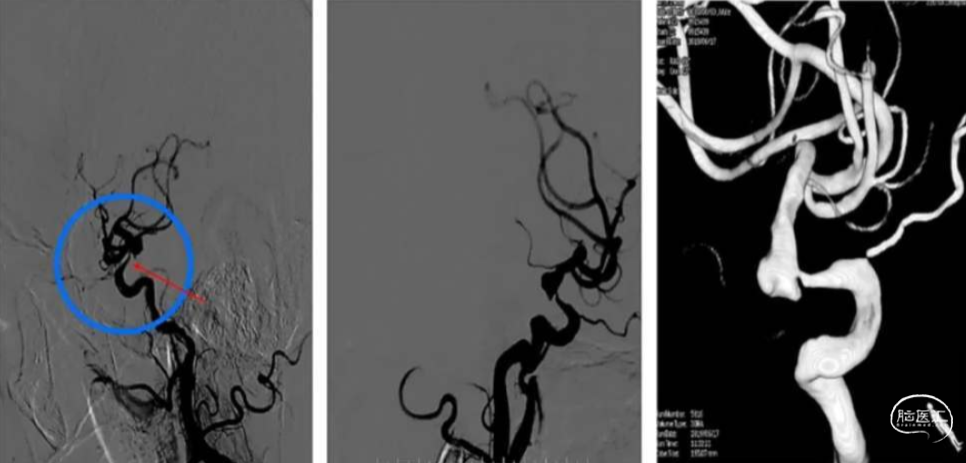

术前脑血管造影及3D重建

高分辨磁共振

1.动脉瘤形态不规则合并子囊,绝对宽径,需支架辅助

2.载瘤动脉近端狭窄

3.同侧A1发育不良